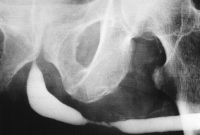

Nach Füllung der Blase mit einem Kontrastmittel, immer mittels Katheter (z.B. via suprapubischen Katheter) wird die normale Miktion unter Röntgendurchleuchtung beobachtet. Damit ist auch eine funktionelle Aussage möglich, ebenso werden pathologische Strukturen im Bereich der Urethra erkannt.

Einspritzen von Kontrastmittel entgegen der physiologischen Flussrichtung des Urins in die Harnröhre. Damit werden speziell Strikturen der Harnröhre bildlich dargestellt.